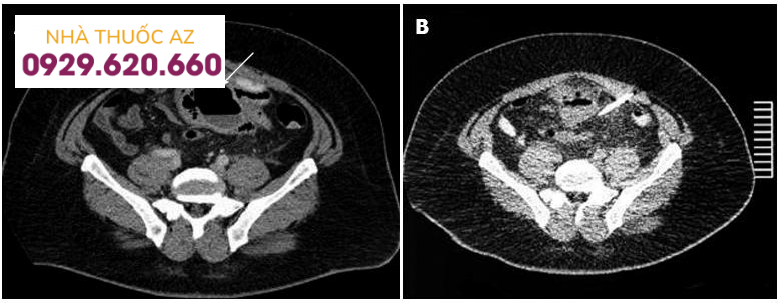

Hình A: Ổ áp xe do VTTĐT xích ma (mũi tên) Hình B: Ổ áp xe sau khi dẫn lưu một tuần (Mũi tên ODL) (Nguồn: Stocchi L. (2010), “Current indications and role of surgery in the management of sigmoid diverticulitis”, World J Gastroenterol, Vol.16 (7), p.804-817)

Ngoài vai trò chẩn đoán, CT còn đóng vai trò như một phương tiện điều trị. Trong VTTĐT với biến chứng áp xe lớn, dẫn lưu ổ áp xe xuyên da dưới hướng dẫn của CT được thực hiện giúp thoát lưu mủ, làm giảm hiện tượng viêm, giúp bệnh nhân tránh một cuộc mổ cấp cứu với phương pháp cắt đoạn ĐT, làm hậu môn nhân tạo (HMNT) và nối ở thì hai. Sau khi dẫn lưu và điều trị nội khoa từ 2 đến 4 tuần, tình trạng viêm giảm và bệnh nhân được lên chương trình mổ với phương pháp cắt đoạn ĐT và nối một thì. Với phương cách như trên, bệnh nhân chỉ phải trải qua một cuộc phẫu thuật thay vì hai cuộc và nhất là không phải mổ cấp cứu. Vì vậy, bệnh nhân sẽ được hưởng rất nhiều lợi ích đồng thời giảm chi phí và thời gian điều trị.